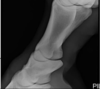

Flexed LateroMedial –> FETLOCK

Flexed DorsoPalmar –> FETLOCK